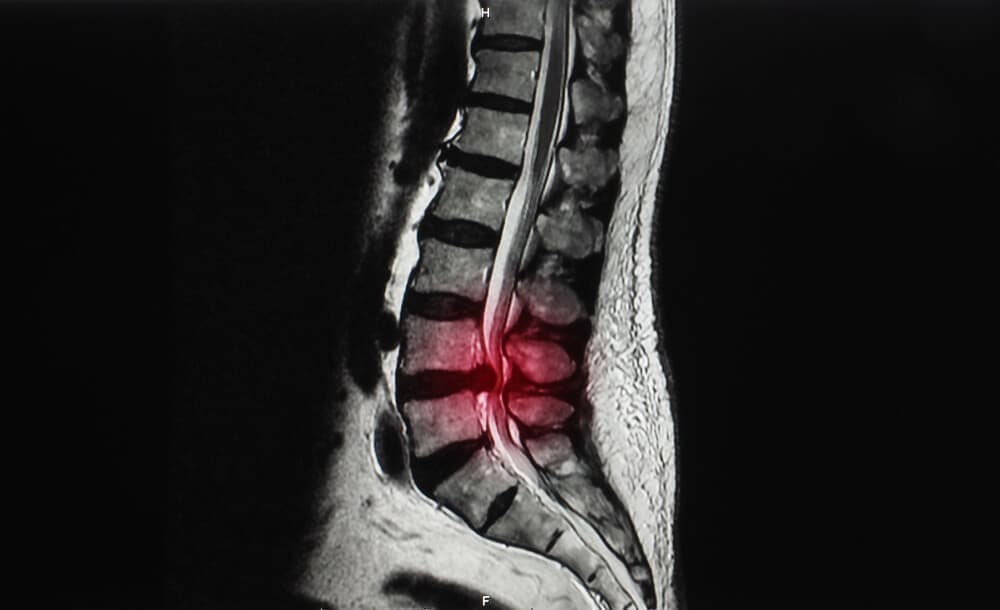

Before

After

脊柱管狭窄症とは?

体を支える脊柱(背骨)は、一つ一つのブロックである椎骨が約32個から34個連結してできています。

その椎骨には穴が存在し、背骨として形成されたときには脊柱管という脊髄・血管が走る道が作られます。

その脊柱管が加齢などの原因でズレが生じ、椎骨と椎骨の間の間隔が狭まったときに発症するのが脊柱管狭窄症です。

椎骨と椎骨の間隔が狭くなると、内部を走っている脊髄や血管が上下から圧迫されます。

それにより、痛みやしびれ(坐骨神経痛)といった症状が現れます。